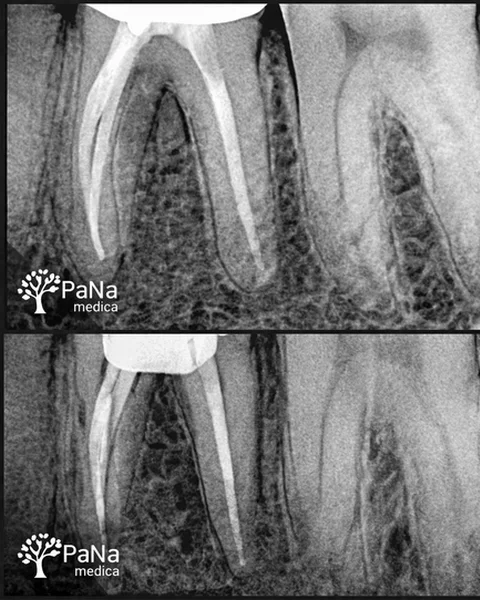

Stomatolog, endodonta / ponad 6 lat doświadczenia

„Zajmuję się leczeniem kanałowym i trudnymi przypadkami. To praca, w której nie ma miejsca na „mniej więcej” — liczy się precyzja i każdy detal.”